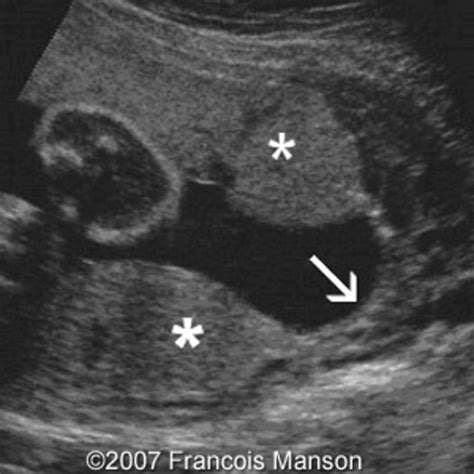

A low lying placenta is typically diagnosed during a routine ultrasound examination. Ultrasounds are usually performed between 18 and 22 weeks of pregnancy to assess the position of the placenta. If the placenta is low-lying at this stage, follow-up ultrasounds may be recommended to monitor its position as the pregnancy progresses.

In some cases, a transvaginal ultrasound may be performed to get a more detailed view of the cervix and placenta. This procedure involves inserting a small ultrasound probe into the vagina and is generally safe and painless.

• low lying placenta ultrasound